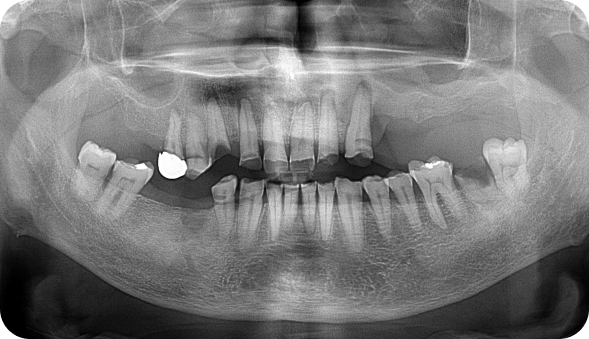

CASE B

환자명 : 정OO 2025.05.20 업데이트

수술 전 촬영일자 : 2023.11.08

수술 후 촬영일자 : 2024.09.27

수술 전(Before)수술 후(After)